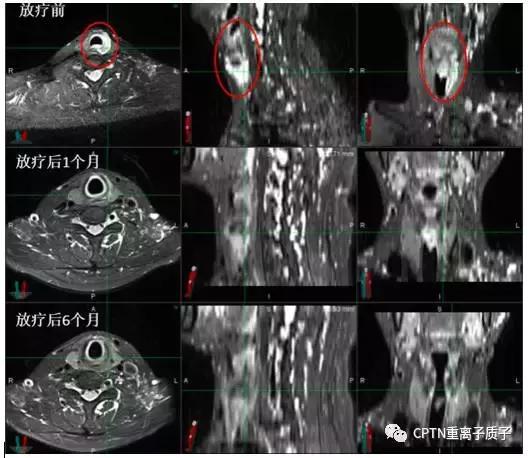

例:

气管腺样囊性癌患者一例。肿瘤生长在上段气管内,如手术则无法保留喉发声的功能。经过重离子根治性放疗,放疗结束后1个月肿瘤就几乎完全消失,目前已无瘤生存超过6个月。治疗仅造成轻度声音嘶哑、食管炎和皮肤反应,且上述反应在治疗后1月几乎完全消失。

图为高危局限期前列腺癌患者,初诊 PSA最高达21.359ng/ml。既往有高血压、冠心病等内科基础疾病,手术风险大,后行根治性重离子治疗联合内分泌治 疗。治疗结束后复查PSA:0.221ng/ml,复查MRI提示前列腺肿瘤从治疗前2.1*1.9cm缩小到0.8*0.8cm(如图所示,红色圆圈部分)。治疗后半年随访PSA:<0.003ng/ml,治疗及随访过程中未出现尿*禁失**、排尿困难等并发症,可以正常参加各类社会活动。